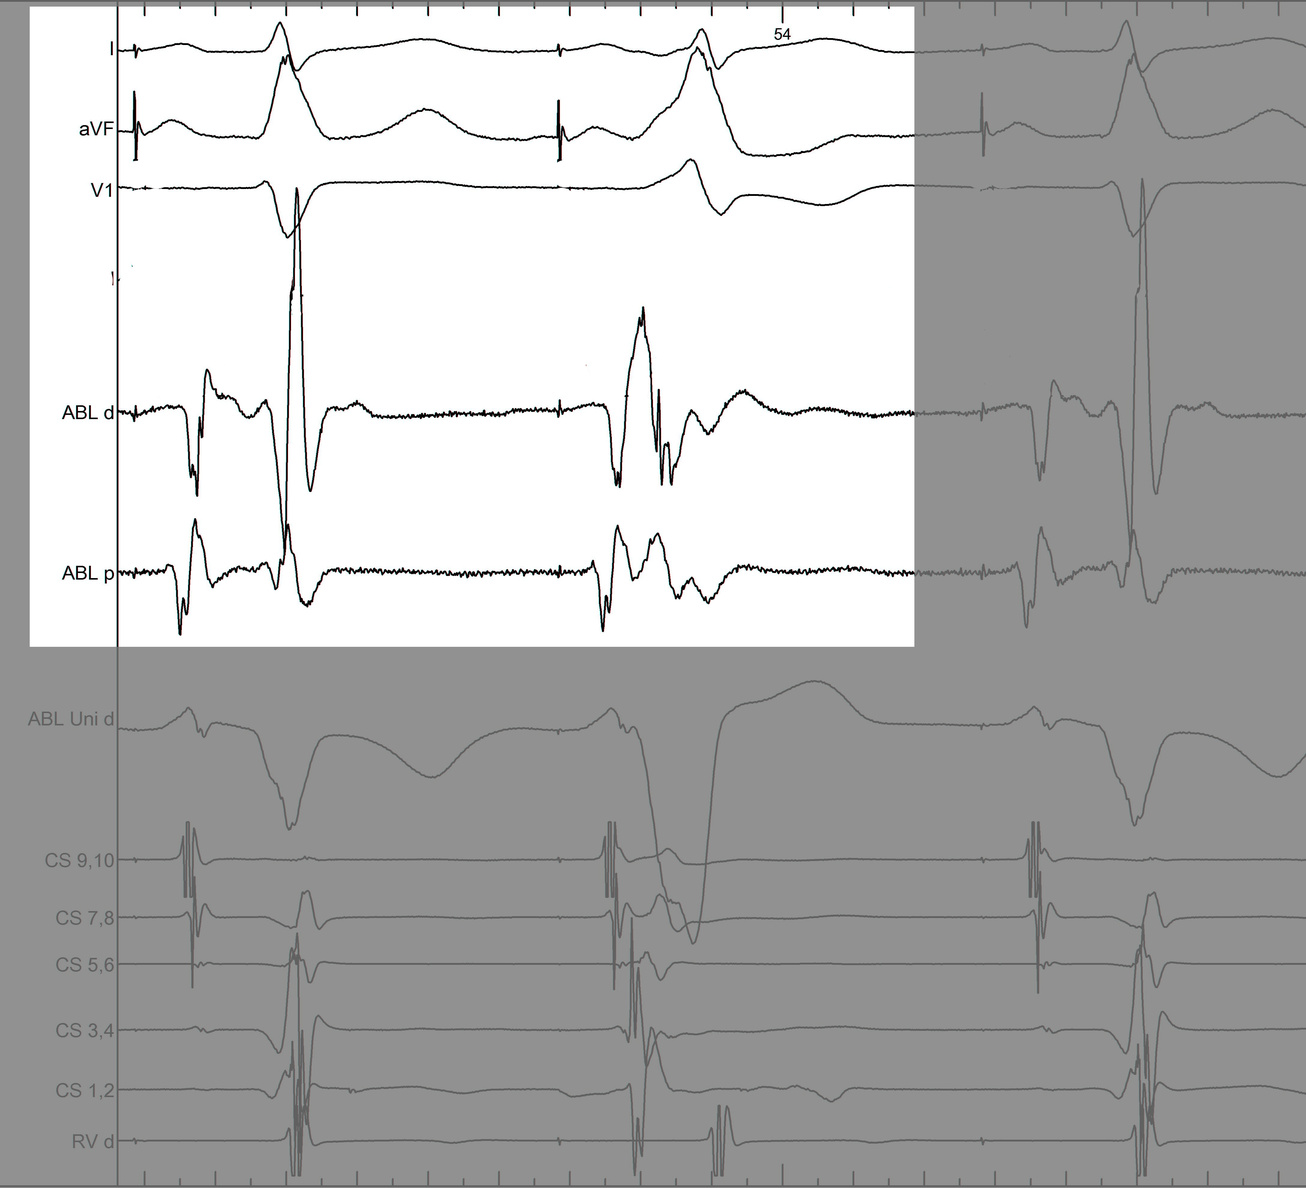

Mapping in diverticulum

signals.jpg

Mapping in diverticulum - CSE potential most important

div_schematic.jpg

Selvaraj RJ et al. Radiofrequency ablation of posteroseptal accessory pathways associated with coronary sinus diverticula. J Interv Card Electrophysiol. 2016 Nov;47(2):253-259. doi: 10.1007/s10840-016-0113-x.